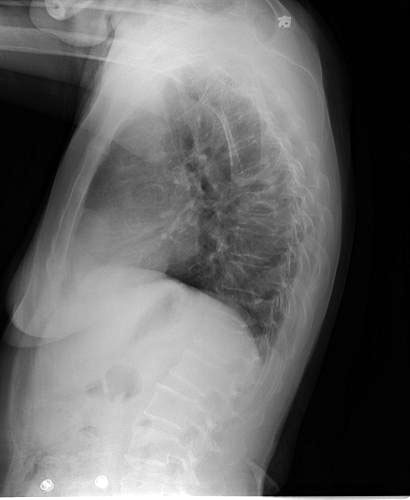

女性 45岁 患肾病综合症1年 有长期使用激素史 现诉背部疼痛。

椎弓根无破坏,椎间隙正常存在,椎旁未见软组织肿块,结核及转移可见除外吧,考虑压缩性骨折

骨质疏松所致的压缩性骨折

上不着村下不着店,胸骨也未见到,很难定位。结合病史考虑为骨质疏松所致多发性胸椎骨折合并节段性胸髓损伤。

考虑骨质疏松所致多发压缩性骨折。